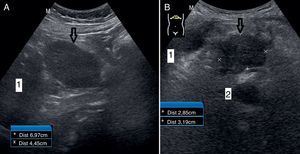

Caso 3. Mujer de 65 años, intervenida por hernia de hiato hace 6 años. Hace un año consulta por pirosis y dolor retroesternal que empeora con la ingesta de determinados alimentos, a pesar de omeprazol. Rechaza hacerse pruebas complementarias, se añaden procinéticos con mejoría. Actualmente, vuelve a consultar por empeoramiento de síntomas. La exploración fue normal, aumentando las dosis de omeprazol y domperidona. Diez días más tarde consulta por pérdida de peso por intolerancia a alimentos; se pide analítica y una endoscopia, y se realiza ecografía en AP al día siguiente, en la que presenta vesícula biliar muy distendida sin ecos en su interior; en zona del hilio biliar presenta colédoco aumentado de 12mm y signo del doble carril. En el páncreas, el colédoco de 16mm y el conducto de Wirsung de 2,5mm (fig. 2A). La analítica realizada ese día presentó (en U/L) GGT 3.991, fosfatasa alcalina 1.569, transaminasas 188 y 292, y bilirrubina total 1,3mg/dl. Tras ser enviada a Digestivo por circuito rápido, se diagnostica mediante TC y ecoendoscopia un ampuloma T3N0 y se indica cirugía.

Caso 4. Varón de 75 años, con antecedentes de hipertensión, diabetes, cardiopatía isquémica, insuficiencia renal crónica y demencia vascular. Presenta molestias abdominales difusas, anorexia y un vómito; analítica (en U/L) con GGT 648, fosfatasa alcalina 538, transaminasas 299 y 115, y bilirrubina total 2mg/dl. Ante esta analítica, se realiza una ecografía en AP donde se visualiza una imagen hipo/anecogénica en la zona de la cabeza de páncreas de 2cm (fig. 2B), sin contenido ni septos en su interior, y vesícula biliar con contenido ecogénico. Se deriva a Digestivo por circuito rápido, comprobando en la TC y la resonancia magnética (RM) una imagen en proceso en el uncinado pancreático, que indica cistoadenoma mucinoso. El paciente mejora espontáneamente, tanto clínica como analíticamente, por lo que se ha demorado la ecoendoscopia diagnóstica y se mantiene actitud expectante, dada la situación basal del paciente, la etiología probablemente benigna del proceso y la resolución del episodio de obstrucción de la vía biliar.